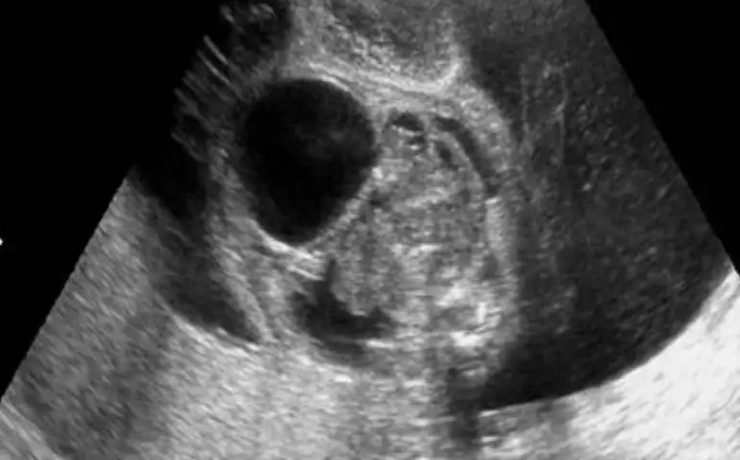

El desarrollo embrionario y fetal del riñón y de las vías urinarias es un proceso biológico extraordinariamente complejo. La formación del riñón definitivo se inicia a partir de la quinta semana de vida intrauterina y su desarrollo depende de la interacción de sus dos compartimientos tisulares; la yema ureteral que